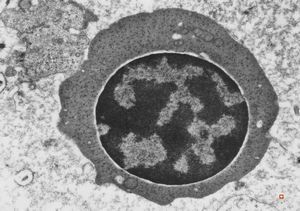

F,50y. | blood … lymphocyte and thrombocyte